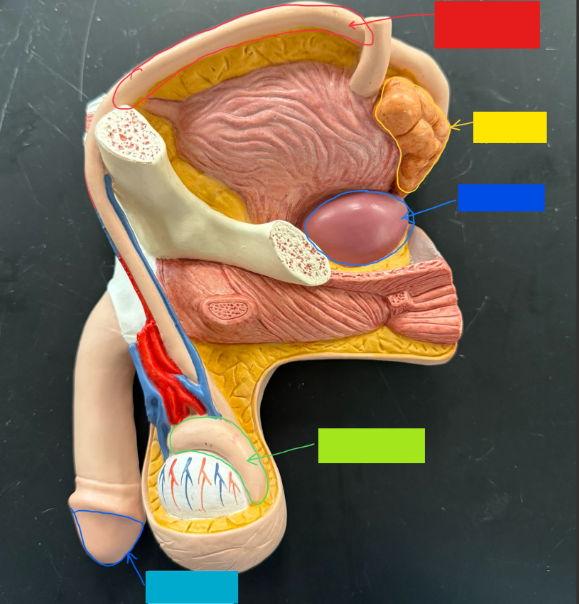

What is the name of the purple box?

Rectum

What is the name of the yellow box?

Anus

What is the name of the red box?

Scrotum

What is the name of the orange box?

Corpus cavernosum

What is the name of the light blue box?

Spongy urethra

What is the name of the pink box?

Ejaculatory duct

What is the name of the yellow box?

Membranous urethra

What is the name of the brown box?

Testis